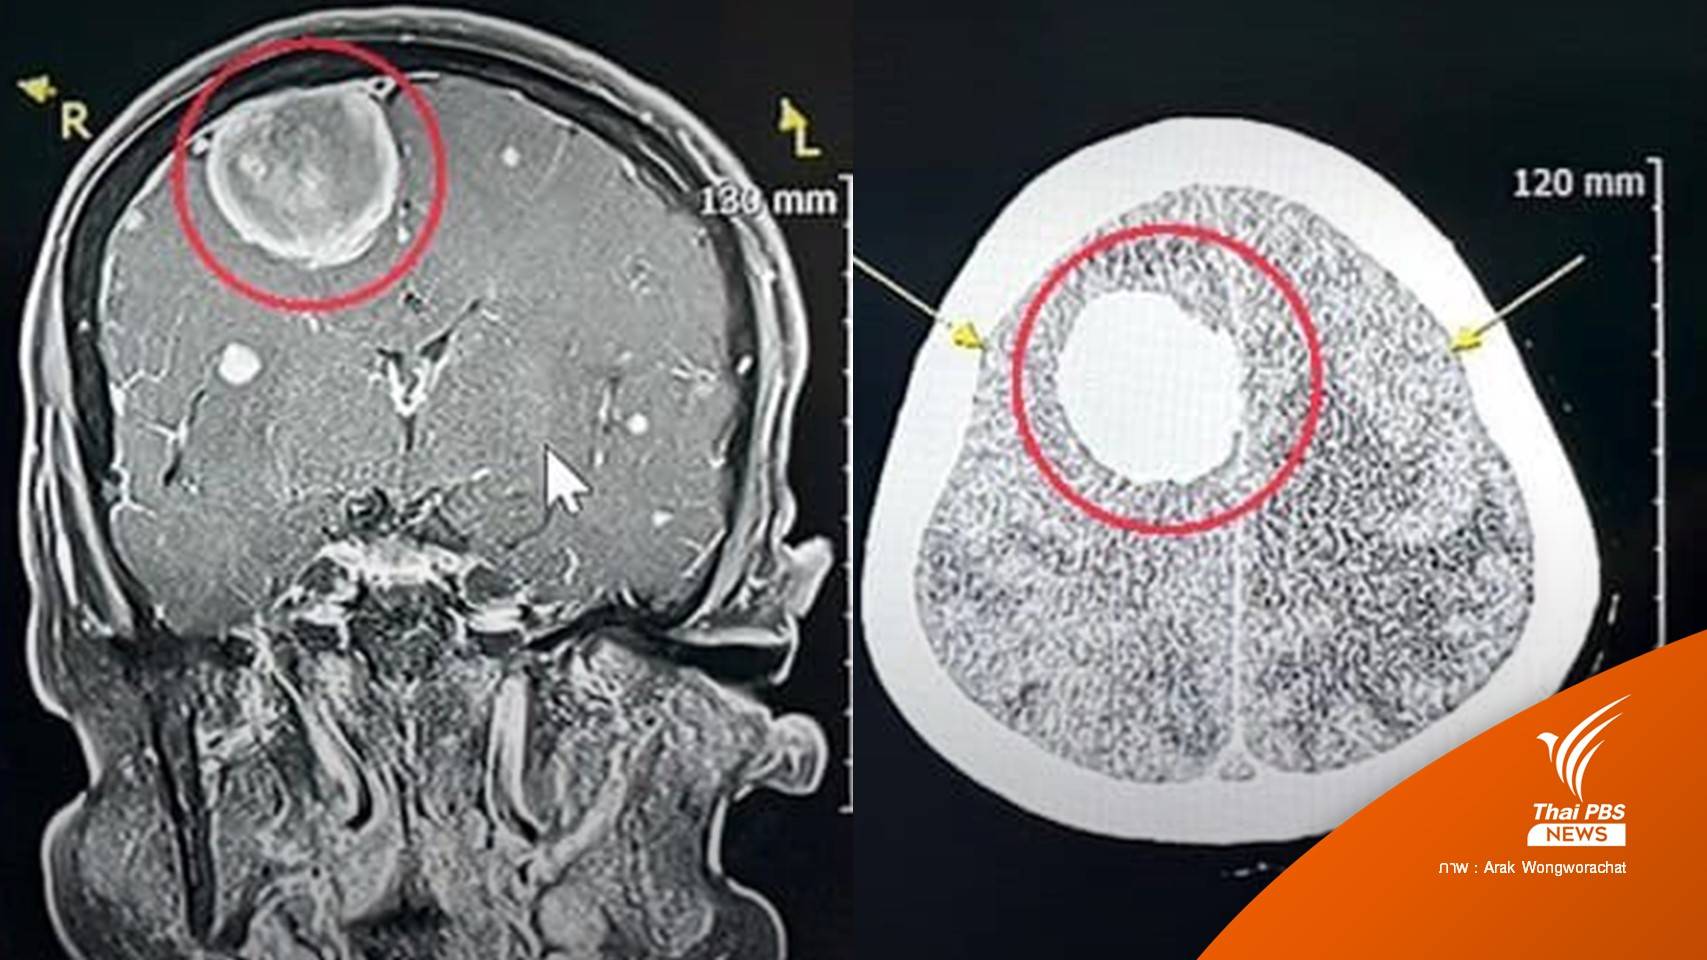

แพทย์เวรตรวจเบื้องต้น สงสัยอาการทางสมอง จึงส่งตรวจคลื่นแม่เหล็กไฟฟ้าสมอง พบเนื้องอกในสมองขนาด 3 เซนติเมตร จึงแนะนำให้นอนโรงพยาบาล วางแผนผ่าตัด ส่งปรึกษาแพทย์ผู้เชี่ยวชาญด้านประสาทศัลยศาสตร์ นัดผ่าตัดสมอง เอาก้อนเนื้อออกมาเป็นผลสำเร็จ โดยไม่มีผลต่อการทำลายเนื้อสมอง สามารถผ่าเอาเนื้องอกออกมาได้ทั้งก้อน